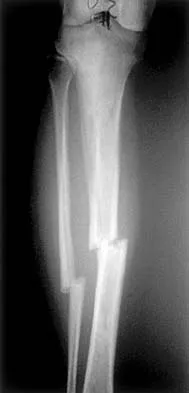

Figures 22a and 22b show the radiographs of a patient who reports stiffness of the hip and associated pain. Management should consist of

The patient has grade IV heterotopic ossification with the limb in an abnormal nonfunctional position. Treatment should consist of excision of the bone to restore hip motion and prophylaxis to prevent recurrent formation. The best time to excise the bone is controversial, with no conclusive evidence supporting early or late excision. Pellegrini VD Jr, Koniski AA, Gastel JA, Rubin P, Evarts CM: Prevention of heterotopic ossification with irradiation after total hip arthroplasty: Radiation therapy with a single dose of eight hundred centigray administered to a limited field. J Bone Joint Surg Am 1992;74:186-200.

- Warren SB, Brooker AF Jr: Excision of heterotopic bone followed by irradiation after total hip arthroplasty. J Bone Joint Surg Am 1992;74:201-210.